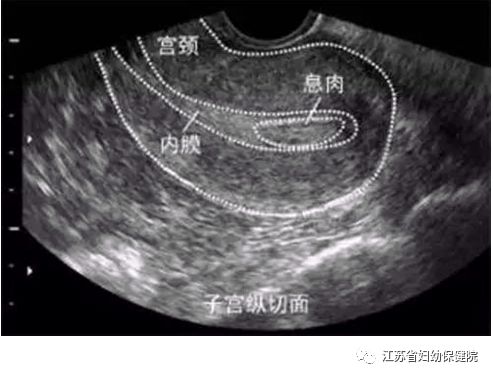

阴道超声

是目前最常用的评价子宫内膜的方法,典型超声特点是宫腔内边界清楚的中高回声结节伴有较粗大条状穿入血流信号。阴超与传统腹部超声相比,因其紧贴阴道后穹窿,排除了肥胖、肠管积气等影响因素,能够获得更高清图像,且具有经济、无创、无痛、可重复性高的优点。但息肉较小时,不易鉴别子宫内膜增生症、子宫内膜息肉及黏膜下肌瘤,误诊率较高。